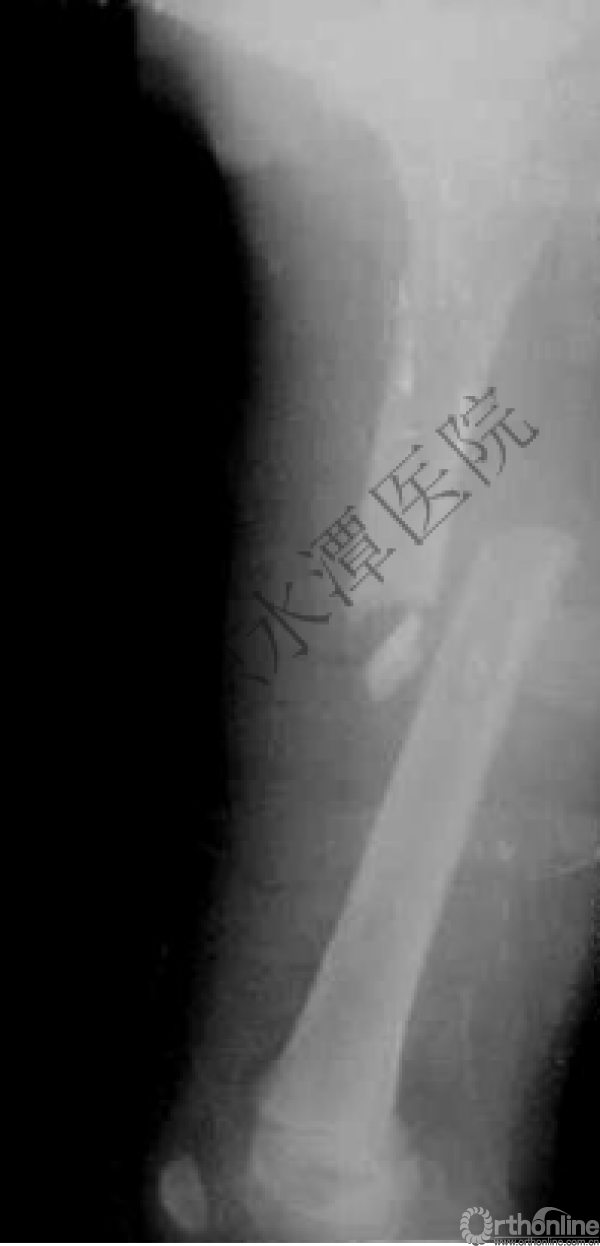

病例分享三

男孩、9岁,滑雪受伤,胫腓骨螺旋形骨折(粉碎性)

这个病例郭教授在积水潭医院骨科高研班时多次讲到,也在互动交流中惊人地看到,了解到现实之令人难以想象!

手法整复,石膏制动!

整复后7天

儿童具备强大的愈合潜力,同样也有极强的塑形能力